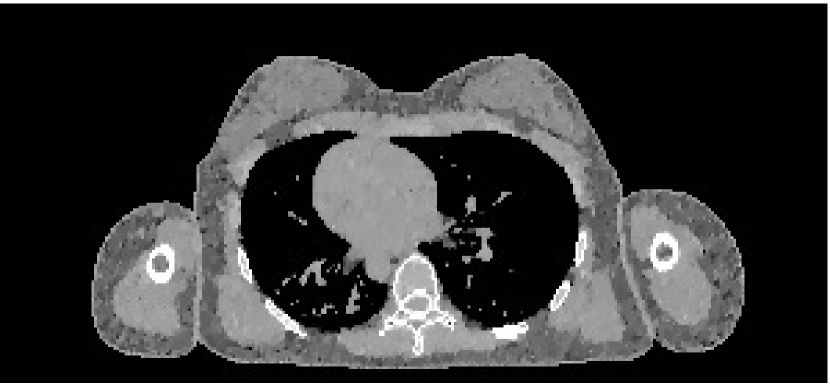

The data we used for our numerical reconstruction test were derived from the Adult Reference Computational Phantom (ICRP Publication 110,, 2009), which is a segmented image of defined density and chemical composition to represent real tissues. To investigate the ability to image metal implants, we inserted a pair of prosthetic hip joints (marked in green) with a solid titanium pin and shell. The slices through the chest and pelvis—which are the images we selected for testing—are shown in Figure 8. The resolution is 299×137299137299\times 137.

Refer to caption

(a) Chest test image

(b) Pelvis test image

Figure 8: Experimental data used: (a) is the oracle chest electron density; and (b) is the oracle pelvis electron density; both have a with display window of [0.8,1.2]